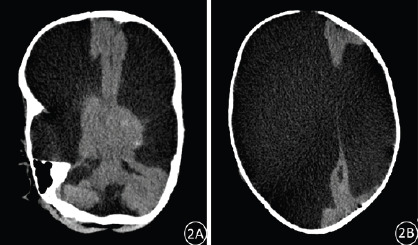

Results: At birth, the primitive reflexes were generally preserved in these infants, who exhibited a spectrum of symptoms including progressive enlargement of head circumference, epilepsy, cerebral palsy, intellectual disability, developmental delay, lethargy, convulsive spasms, and varying degrees of visual and auditory impairment. These infants may also present with other congenital malformations or abnormalities. The primary CT imaging findings revealed complete or near-complete absence of bilateral cerebral hemispheres, replaced by CSF. Specifically, there were 5 cases of complete absence of cerebral hemispheres, with minimal residual brain tissue observed in 17 cases. Bilateral ventricles were approximately normal in 3 cases and completely absent in 19 cases. Falx cerebri was incomplete or/and displaced in 12 cases, and 3 cases were concurrent with Dandy-Walker syndrome.

Conclusion: Hydranencephaly is a congenital disease characterized by destruction of the cerebral hemispheres. CT scan can provide accurate and reliable imaging evidence for the diagnosis of hydranencephaly.